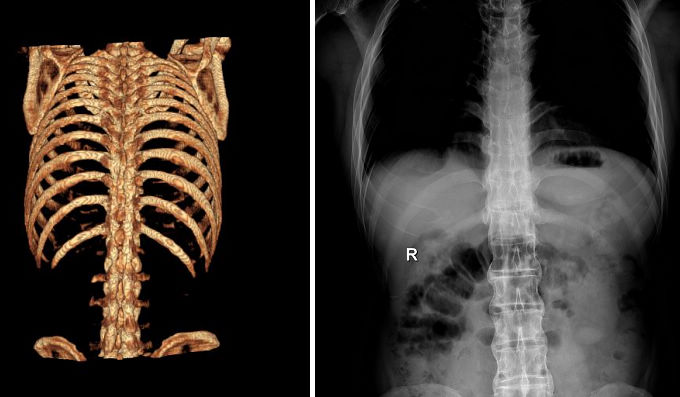

AS ①晚期 ②重度 病史:5年+

- 治疗

治疗后骶髂关节疼痛消失,腰椎前屈、背伸侧弯活动自如,膝关节无压痛感,复查血沉、C反应蛋白、等各项检查均已达到临床康复的标准。